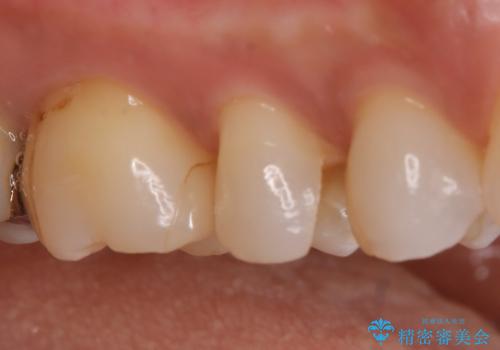

【セラミックインレー】昔治療した詰め物が外れた。

- 他院でいれたセラミックインレーが脱離して、来院されました。

新たに製作を希望されたため、当院で治療しました。

当院でのセラミックインレーの治療は、ラバーダムを使用しています。